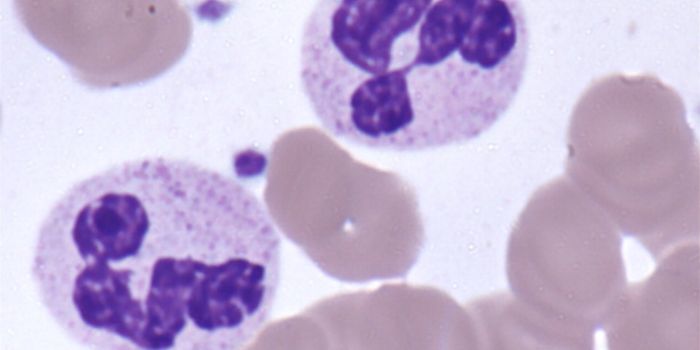

MAY 21, 2018CancerThe malarial parasite expresses a protein, VAR2CSA, that binds to chondroitin sulfate (CS) found on both placental and c ...